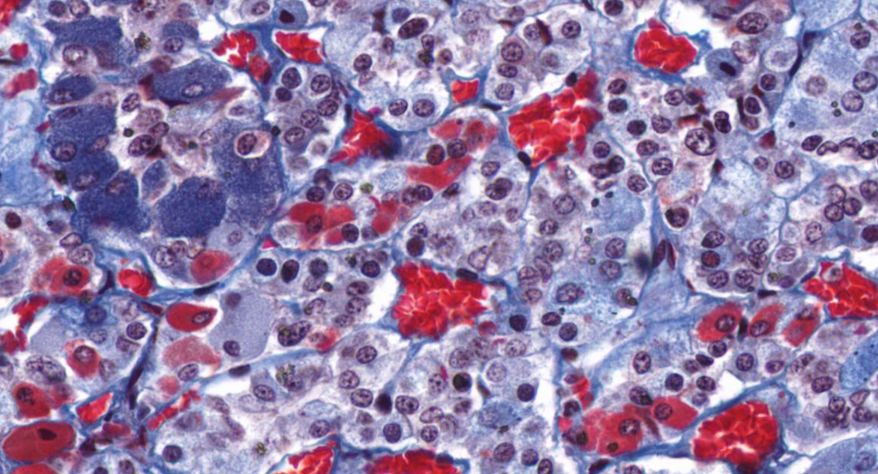

低倍镜:分出皮质及髓质。皮质由表至里分为三个带:高倍镜:(1)皮质:①球状带的细胞聚集成球状团块,细胞较小,矮柱状或多边形,核小,着色深,胞质弱嗜碱性,有少量脂滴。②束状带很厚,细胞排列成束状,在细胞之间有少量结缔组织及丰富的血窦,高倍镜观察束状带的细胞体积较大,呈多边形,核大而着色浅,胞质有许多脂滴,在制片过程中被溶解,因此胞质染色很淡。③网状带细胞排列成索,细胞索互相吻合成网,索间有丰富的血窦,胞质染色略呈嗜酸性,脂滴很少,核小着色浅。(2)髓质:髓质和皮质交界参差不齐,髓质细胞较大,呈多边形,此外还有少量交感神经节细胞,后者胞体较大,胞质着色浅,常单个或2~3个成群散布于髓质内。

1.全景图

2.被膜

3.皮质

4.球状带(10x)

5.球状带(40x)

6.束状带(10x)

7束状带(40x)

8.网状带(10x)

9.网状带(40x)

10.网状带细胞内脂褐素

11.髓质

12.嗜铬细胞

13.交感神经节细胞

14.中央静脉